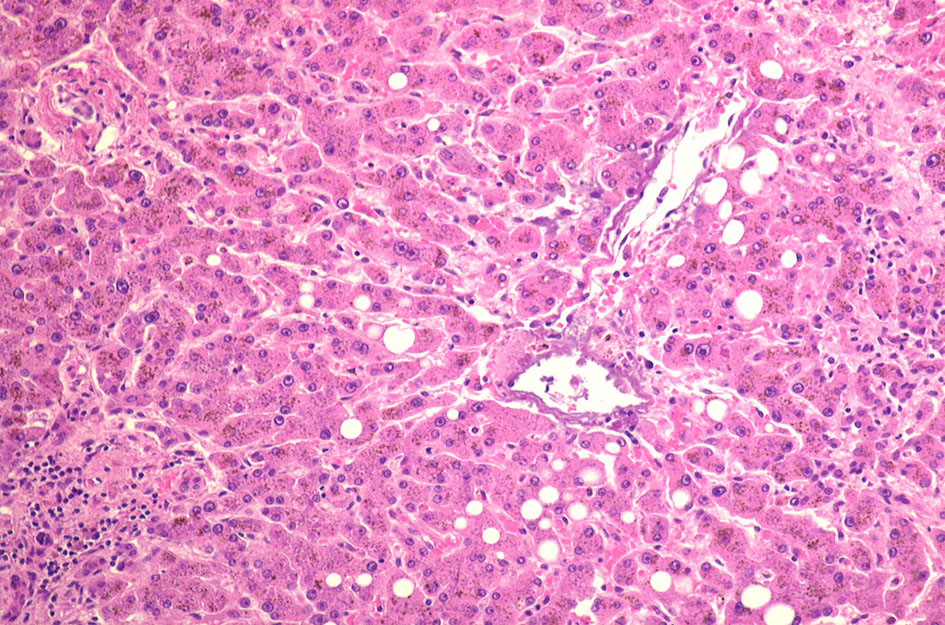

肝ヘモジデローシス 70歳代男性 胃癌術後B-II胃全摘術後

肝障害はトランスアミナーゼ上昇に始まり, 進行すると肝線維症, 肝硬変を来たし, 症例によっては肝癌を発症する。

心筋障害は初期には拡張障害として出現し, その後, 収縮能低下が顕在化して心エコー上左室駆出率(left ventricular ejection fraction; LVEF)が低下する。

膵ではβ細胞の破壊に伴って耐糖能低下が進行する。